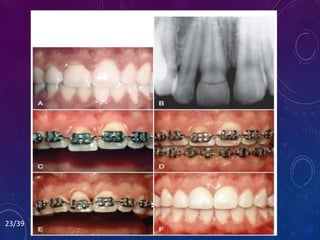

Occasionally,

# may extend beneath

Restoration of the #

the bone.

persistent

of the bone & move

if the # extends too

bridge.

FRACTURED TEETH/FORCED ERUPTION

• 6 criteria determine whether the tooth should be forcibly

erupted or extracted.

1. Root length

2. Root form

3. Level of fracture

4. Relative importance of tooth

5. Esthetics

6. Endodontic/periodontic prognosis

• The orthodontic mechanics necessary to erupt the tooth can

vary from elastic traction to orthodontic banding and

bracketing.

24/39

Occasionally, children and adolescents mayfall and injure their anterior teeth. # may extend beneath the level of the GM & terminate at the level of the alveolar ridge. Restoration of the # crown is impossible because the tooth preparation would extend to the level of the bone. overextension of the crown margin - invasion of the BW of the tooth - persistent inflammation of the marginal gingiva. It may be beneficial to erupt the # root out of the bone & move the # margin coronally so that it can be properly restored. if the # extends too far apically, it may be better to extract the tooth and replace it with an implant or bridge. FRACTURED TEETH/FORCED ERUPTION

• 6 criteriadetermine whether the tooth should be forcibly erupted or extracted. 1. Root length 2. Root form 3. Level of fracture 4. Relative importance of tooth 5. Esthetics 6. Endodontic/periodontic prognosis • The orthodontic mechanics necessary to erupt the tooth can vary from elastic traction to orthodontic banding and bracketing. 24/39

• #25 This patient had a severe fracture of the maxillary right central incisor that extended apical to the level of the alveolar crest on the lingual side To restore the tooth adequately and avoid impinging on the periodontium, the fractured root was extruded 4 mm. As the tooth erupted, the gingival margin followed the tooth. Gingival surgery was required to lengthen the crown of the central incisor so that the final restoration had sufficient ferrule for resistance and retention and the appropriate gingival margin relationship with the adjacent central incisor`